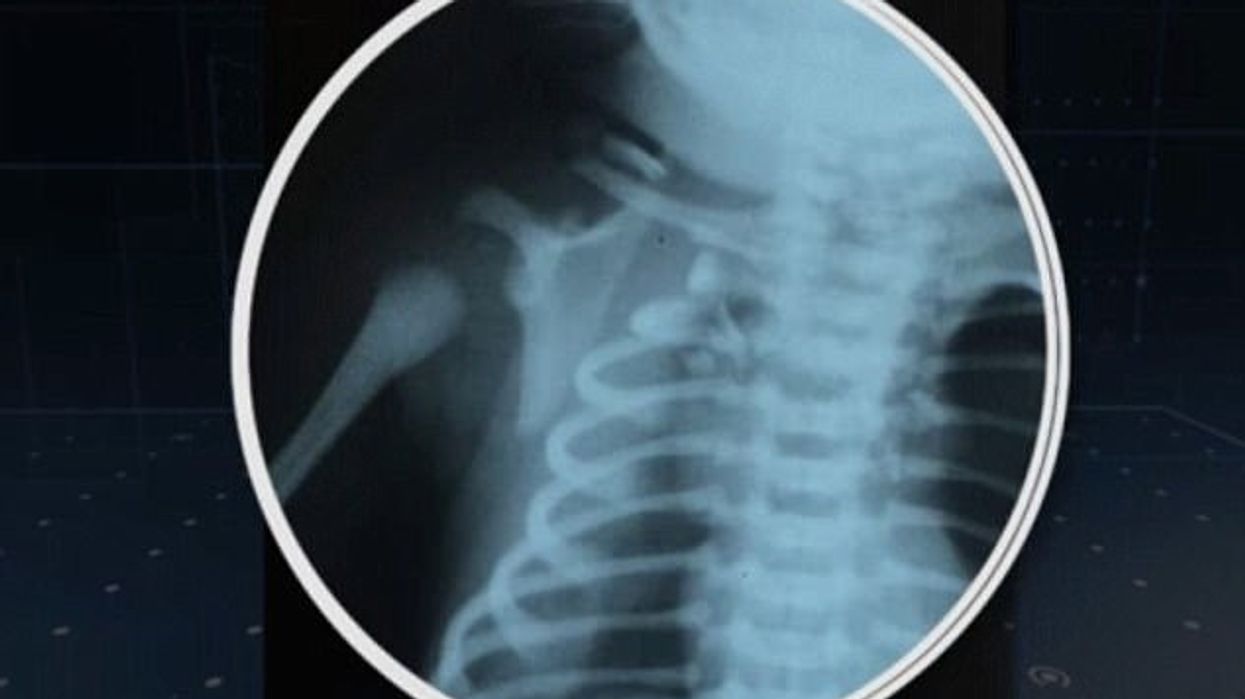

Vogëlushi që u quajt Arthur, kishte marrë lëndime në mushkëri dhe palcën kurrizore, si dhe i është dëmtuar njëri vesh.

Por, pas intervenimit të menjëhershëm, gjendja tij shëndetësore i është kthyer normalitetit.